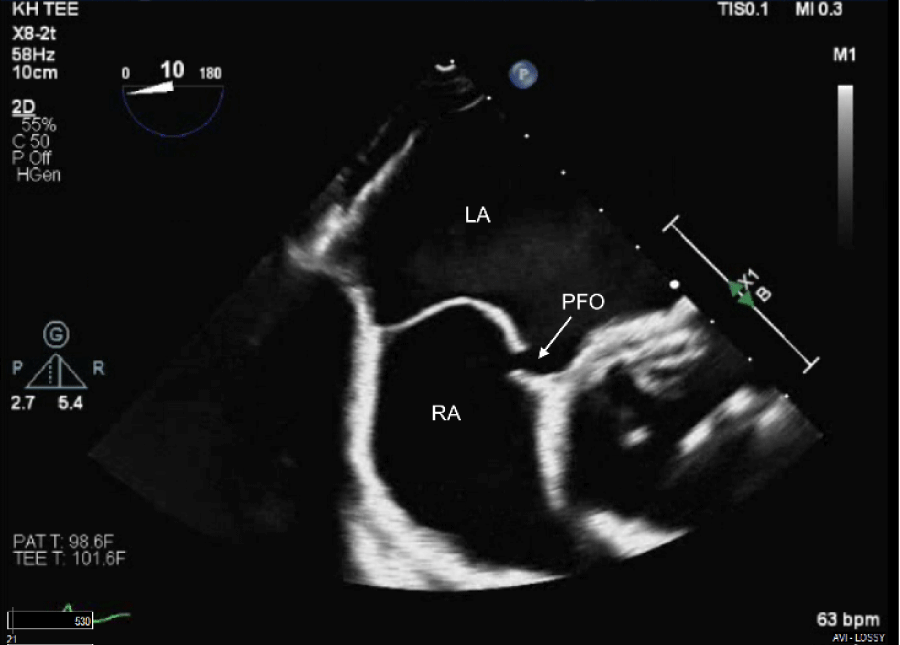

The patient’s clinical condition was consistent with Platypnea-Orthodeoxia syndrome based on the findings described above. A transthoracic echocardiogram indicated an ejection fraction (EF) of 51-55%, with mild left ventricular hypertrophy (LVH) and mild right ventricular dilatation. The bubble study was inconclusive. A transesophageal echocardiogram (TEE) revealed that the interatrial septum was aneurysmal, and a large PFO was visible on color Doppler imaging and following the injection of agitated saline contrast, as shown in figures 1 and 2. The patient underwent transcatheter closure of a patent foramen ovale using a 30 mm Gore Cardioform device, as depicted in figure 3 and 4. Immediately after the procedure, a repeat bubble study was conducted, which showed no bubbles crossing the patent foramen ovale (PFO). He was placed on dual antiplatelet therapy, with aspirin and clopidogrel for one month, followed by aspirin indefinitely. On the day of discharge, the patient was sitting upright in bed with oxygen saturation levels at 94% on room air and reported no shortness of breath. The patient was feeling much improved. The patient's care in the hospital involved a multidisciplinary approach that included teams from cardiology, pulmonology, and hospital medicine. Following hospital discharge, the patient had follow-up appointments in both the cardiology and pulmonary clinics and underwent a transthoracic echocardiogram (TTE) one month after the procedure. The left atrial cavity is moderately dilated. No patent foramen ovale was detected during the agitated saline injection. The patient did not report any breathing issues, and his oxygen saturation on the day of the follow-up was 94%.

Figure 1: TEE with bubbles from RA into LA through PFO. View Figure 1